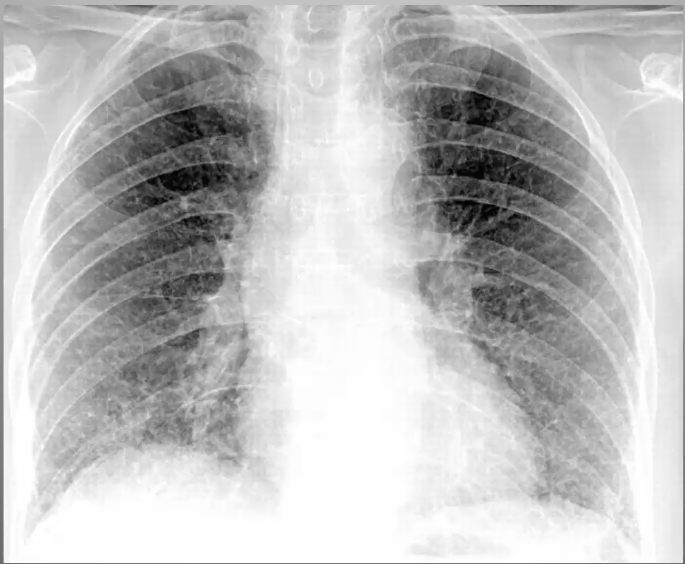

What’s your diagnosis?

Ground Glass: Hypersensitivity Pneumonitis